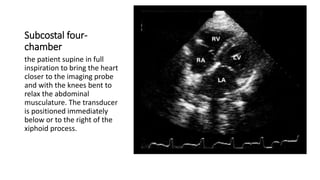

Subcostal four-

chamber

the patient supine in full

inspiration to bring the heart

closer to the imaging probe

and with the knees bent to

relax the abdominal

musculature. The transducer

is positioned immediately

below or to the right of the

xiphoid process.

Subcostal four- chamber the patientsupine in full inspiration to bring the heart closer to the imaging probe and with the knees bent to relax the abdominal musculature. The transducer is positioned immediately below or to the right of the xiphoid process.